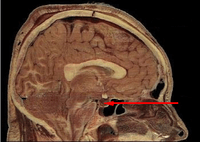

![]() Located at the base of the brain, the pituitary gland is protected by a bony structure called the sella turcica of the sphenoid bone. | |

In vertebrate anatomy, the pituitary gland, or hypophysis, is an endocrine gland about the size of a pea and weighing 0.5 grams (0.018 oz) in humans. It is a protrusion off the bottom of the hypothalamus at the base of the brain. The hypophysis rests upon the hypophysial fossa of the sphenoid bone in the center of the middle cranial fossa and is surrounded by a small bony cavity (sella turcica) covered by a dural fold (diaphragma sellae).[2] The anterior pituitary (or adenohypophysis) is a lobe of the gland that regulates several physiological processes (including stress, growth, reproduction, and lactation). The intermediate lobe synthesizes and secretes melanocyte-stimulating hormone. The posterior pituitary (or neurohypophysis) is a lobe of the gland that is functionally connected to the hypothalamus by the median eminence via a small tube called the pituitary stalk (also called the infundibular stalk or the infundibulum).